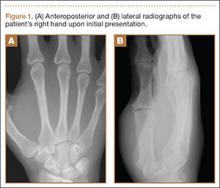

Plain radiographs were unremarkable (Figures 1A, 1B). Magnetic resonance imaging (MRI) with and without contrast revealed a 4×2-cm mass consistent with a diagnosis of lipoma. However, it was unique in that it appeared to extend from the long- and ring-finger extensor tendon sheaths in the fourth dorsal compartment of the hand (Figures 2A, 2B) and was deemed a lipoma of the tendon sheath. Representative MRI also showed the lipoma to be present within the fourth extensor compartment of the hand (Figure 2B). Because of the mass’s increasing size and interference with hand function, the patient elected to have the mass excised.